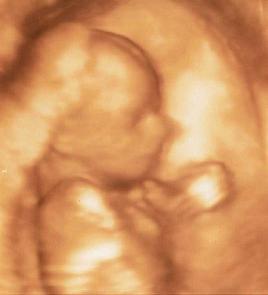

Hoztam Nektek VALAKIT!! Kép :D

milyen gratulálok, gyönyörűséges :D

Köszönöm!Nekünk mindenesetre a legszebb :) :wink:

Még a szívem is beledobbant, olyan jó érzés látni ezt a kis csöppséget! :D

jaaaj, de cukorfalat, hát nagyon szépséges kisbabád van :!: :wink:

Mesélj, milyen volt amúgy az egész mozi :?:

Párocskád élvezte :?: :D Biztos nagyon jó lehetett :!:

Milyen: nagyon helyes!!!!!! De jó lehetett látni!!!! :P